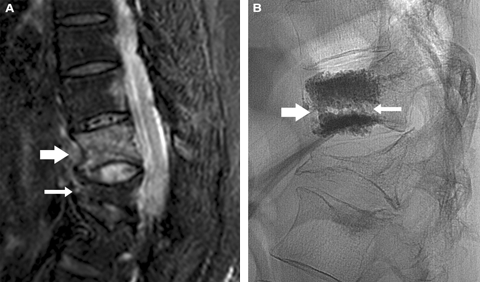

1 Imaging before and after vertebroplasty of an acute osteoporotic fracture in the thoracolumbar spine of a 79-year-old patient 2 weeks after a fall

A: Sagittal short-inversion-time inversion recovery (STIR) magnetic resonance imaging (MRI) scan of the thoracolumbar spine. On this type of MRI scan, fluid provides the only bright signal. This is a midline image, with anterior to the left, showing an acute T12 fracture (broad arrow). Note the dark linear fracture line transgressing the vertebral body. This is not a “crush fracture” but rather an axial transection splitting the vertebral body into inferior and superior halves. There is an old, healed fracture of the L1 vertebral body (thin arrow) which alters the biomechanical strain through the acute T12 fracture line. The lack of bright signal in the

L1 fracture shows this to be long-standing.

B: Vertebroplasty image in the lateral projection. Note the trabecular cement filling in the superior and inferior aspects of the vertebral body, separated by the fracture line (thin arrow). There is an anterior cement column (broad arrow) bonding the two fragments together and providing internal fixation.